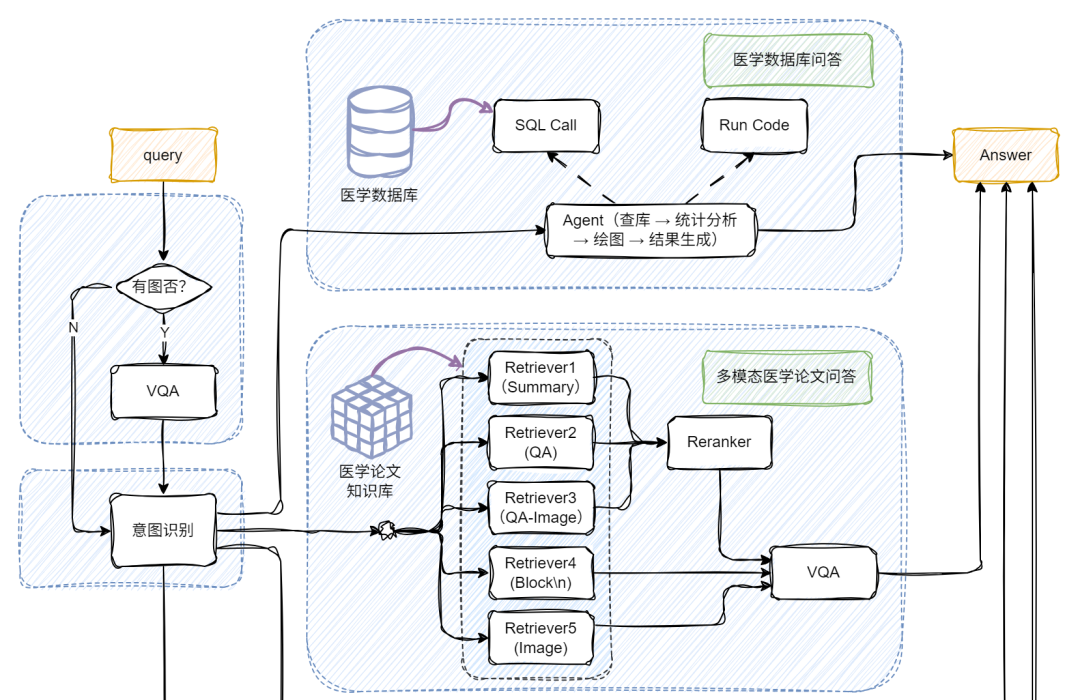

下图和视频效果是我们今天的目标!涉及多路召回多模态RAG、多模态问答、Chat-BI、Agent、LLM微调、多模态模型微调等等。让我们开始吧!

通过前面的探索,我们已经了解了朴素 RAG 如何让大模型具备“查资料再回答”的基础能力,也见证了多模态 RAG 通过图文融合实现的“感官升级”。但当实际应用场景涉及“医院年度病例统计分析”、“科研文献数据可视化呈现”等需求时,单纯的多模态处理仍显不足 —— 这类场景既需要解析医学影像、病历文本等非结构化数据,又要对接数据库完成指标计算、图表生成等 BI任务。

如何让 RAG 系统同时驾驭多模态理解与结构化数据分析?接下来要展开的多模态 + BI复杂架构实战,正是为解决这类“既要又要”的高阶需求而生,我们将在朴素 RAG 基础上层层叠加关键模块,最终打造出能同时处理影像诊断、数据统计、图表生成的全能型 AI 助手!

当用户提问中包含图片时,系统会自动触发 VQA,对图像进行结构化信息提取,挖掘上下文关键内容;若没有图像,就跳过这步,直接进入文本处理环节,效率UPUP!

接下来,系统通过意图识别模块,将不同类型的问题智能分流:

📌论文问答? 走传统 RAG 路线!向量检索+大模型生成,精准提取相关文献内容。

📌统计问答? 开启 SQL 模式!从提问中抽取结构化信息(如指标、维度、过滤条件),自动生成 SQL 查询,查询结果再由大模型“翻译”成自然语言,一目了然!

这部分我们聚焦在医学论文问答场景,结合文本+图像的多模态输入,构建一个更智能的 RAG 系统,并支持返回可视化图表。整体框架的细节如下:

首先,我们将PDF解析成文本和图像;文本部分我们可以通过\n切分、LLM(总结)和 LLM(QA)等方式构造不同的block文本节点;图像部分我们通过多模态大模型构建相应的QA文本节点qapair_img和图像根节点;接下来,我们将所有节点统一编码入库,并通过多路召回机制进行语义匹配与内容检索;在召回阶段之后,引入重排序机制,进一步优化检索结果的相关性与准确性;最后,系统会将用户的查询(query)与召回得到的上下文(context)内容一并输入至多模态大模型,由其生成最终答案。整体代码实现如下: